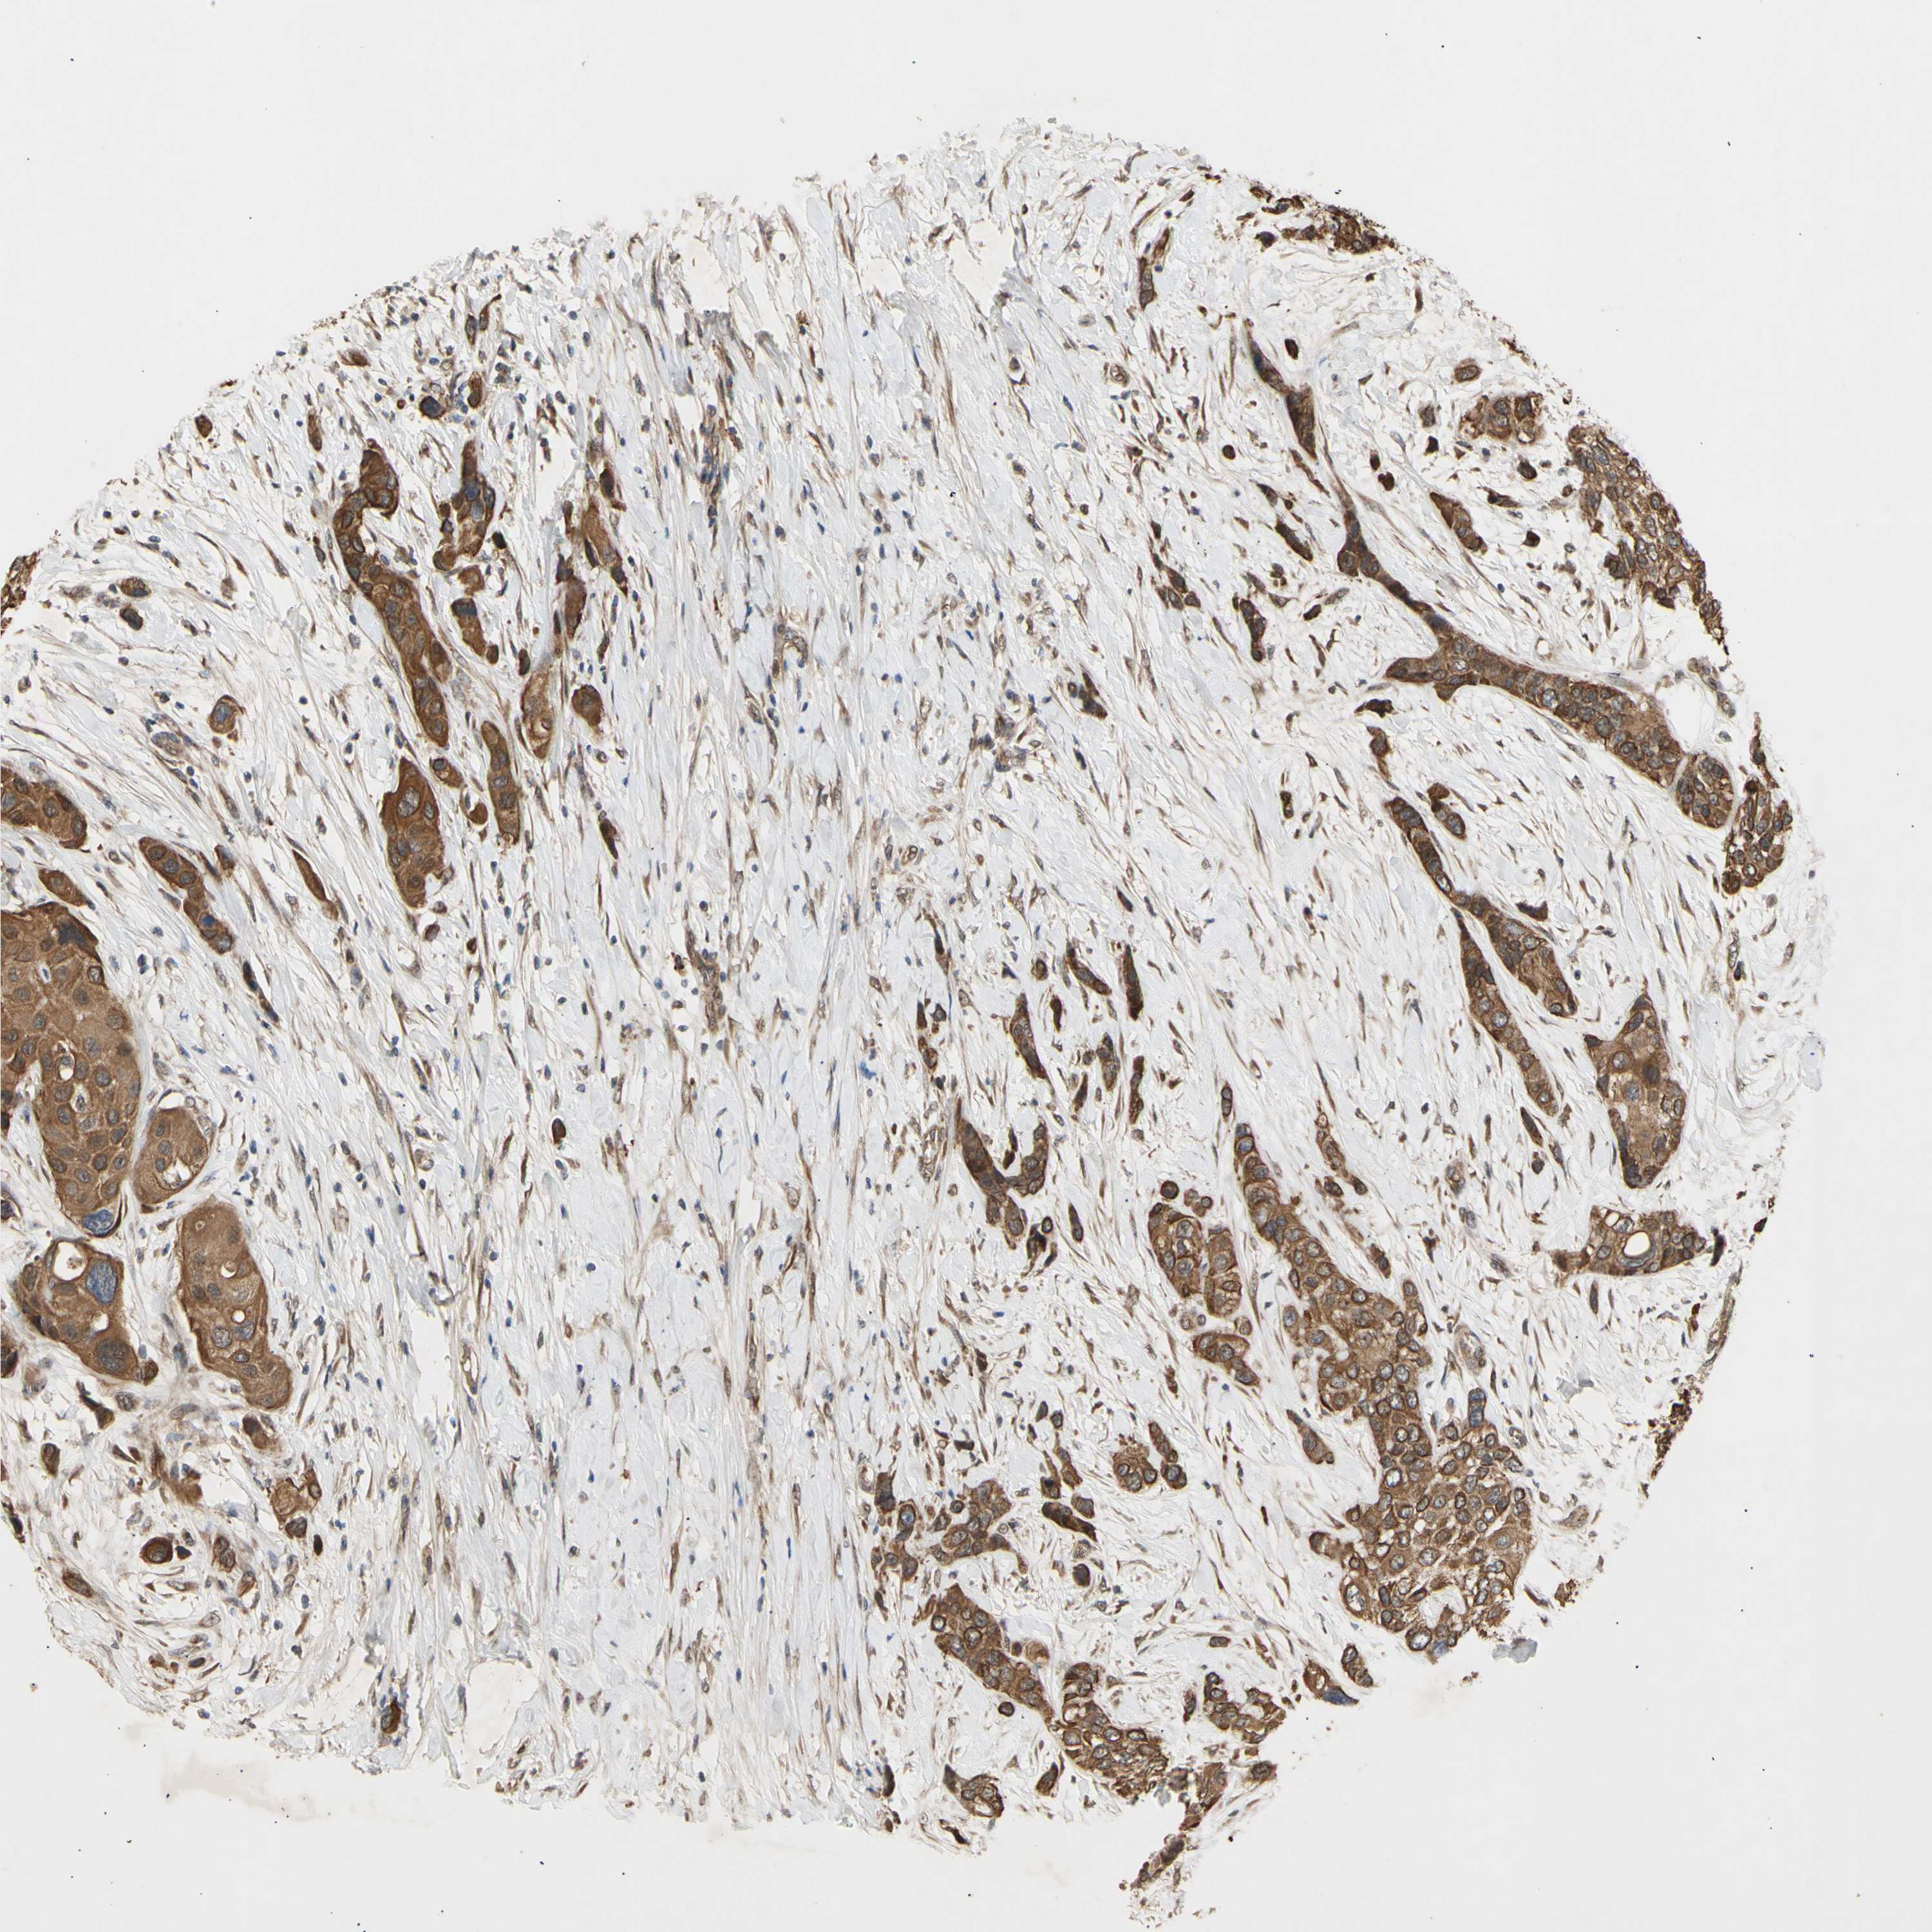

UROTHELIAL CANCER - Protein expressioni

A mouse-over function shows sample information and annotation data. Click on an image to view it in a full screen mode. Samples can be filtered based on level of antibody staining by selecting one or several of the following categories: high, medium, low and not detected. The assay and annotation is described here.

Note that samples used for immunohistochemistry by the Human Protein Atlas do not correspond to samples in the TCGA dataset.

Antibody stainingi

Antibody staining in the annotated cell types in the current human tissue is reported as not detected, low, medium, or high, based on conventional immunohistochemistry profiling in selected tissues. This score is based on the combination of the staining intensity and fraction of stained cells.

Each image is clickable and will lead to virtual microscopy that enables deeper exploration of all samples and also displays staining intensity scores, fraction scores and subcellular localization as well as patient and tissue information for each sample.

Antibody HPA003982

Antibody CAB010278

Staining

High

Medium

Low

Not detected

Intensity

Strong

Moderate

Weak

Negative

Quantity

>75%

75%-25%

<25%

None

Location

Nuclear

Cytoplasmic/membranous

Cytoplasmic/membranous,nuclear

Urothelial carcinoma, High grade

Urothelial carcinoma, Low grade